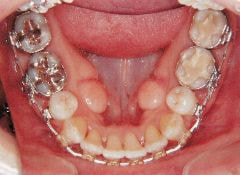

治療例2 (補綴処置+矯正)